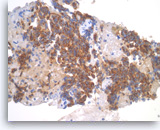

Acinar cell carcinoma,

Pancreas FNA, Cell Block.

The tumor cells are focally positive for chymotrypsin.

40X